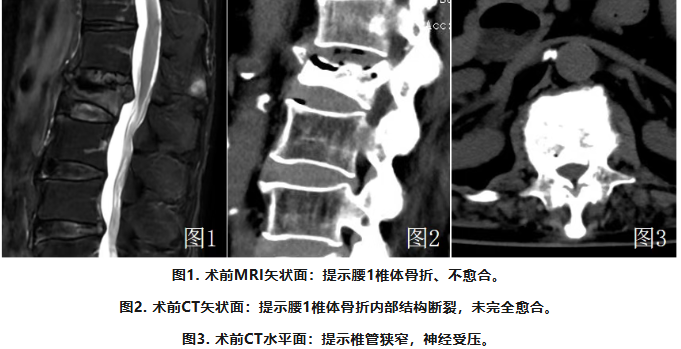

苏阿姨今年73岁,正月就因为骨质疏松导致的腰1椎体骨折,而短暂失去了日常生活质量,在平卧休息近1个月后,才勉强回到日常生活。

在家人陪伴下,她来到我院就诊,经过详细检查,苏阿姨确诊了“腰椎椎体压缩性骨折,胸腰椎椎管狭窄”。